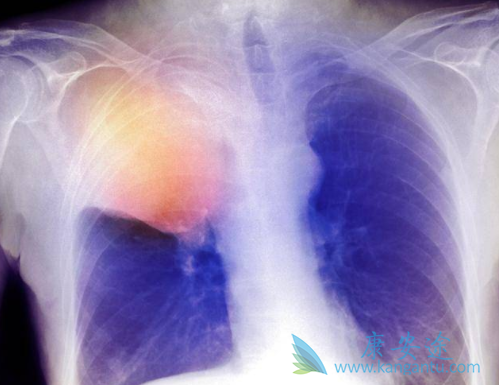

肺癌患者中,3%~8% 有ALK突变。克唑替尼是ALK 融合基因阳性晚期 NSCLC 患者的标准治疗。然而,患者往往在 1~2 年内出现克唑替尼治疗耐药,且中枢神经系统的复发进展较为常见。Lorlatinib是第三代ALK抑制剂,对未接受克唑替尼治疗和克唑替尼耐药的患者均具有活性,并且其对脑转移灶更有效。但Lorlatinib也有不良反应,患者该如何处理呢?